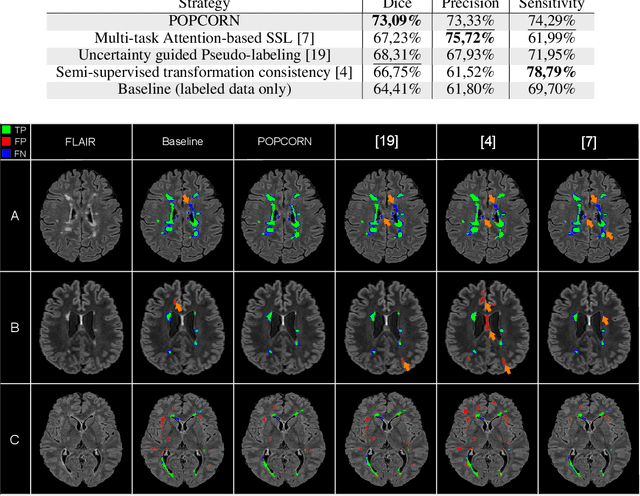

Abstract:Semi-supervised learning (SSL) uses unlabeled data to compensate for the scarcity of annotated images and the lack of method generalization to unseen domains, two usual problems in medical segmentation tasks. In this work, we propose POPCORN, a novel method combining consistency regularization and pseudo-labeling designed for image segmentation. The proposed framework uses high-level regularization to constrain our segmentation model to use similar latent features for images with similar segmentations. POPCORN estimates a proximity graph to select data from easiest ones to more difficult ones, in order to ensure accurate pseudo-labeling and to limit confirmation bias. Applied to multiple sclerosis lesion segmentation, our method demonstrates competitive results compared to other state-of-the-art SSL strategies.